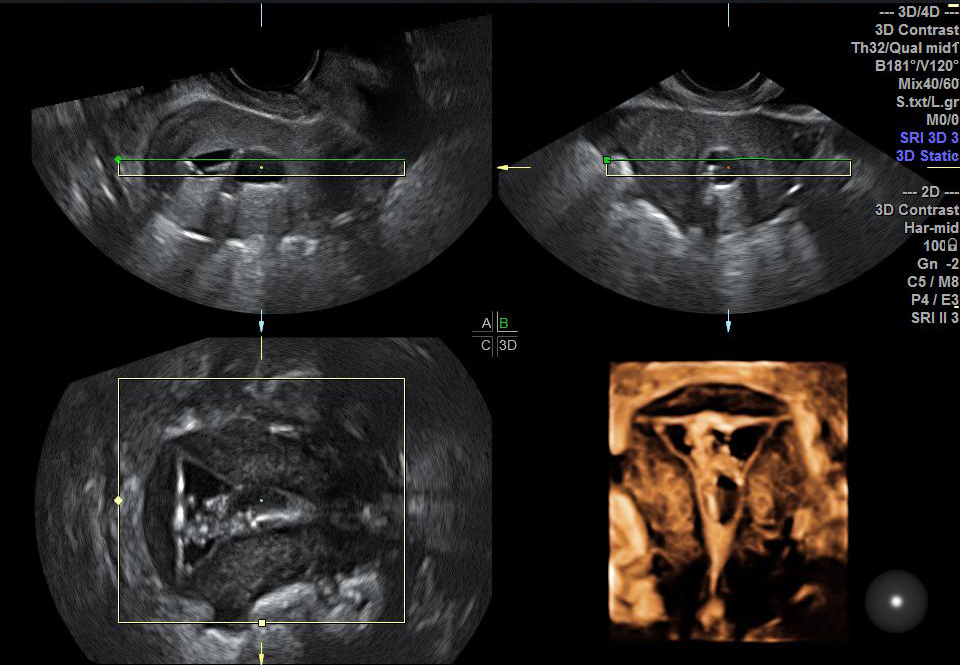

二维超声:观察子宫及双侧卵巢形态和结构变化,对子宫、输卵管、卵巢及盆腔的疾病做基础性排查。